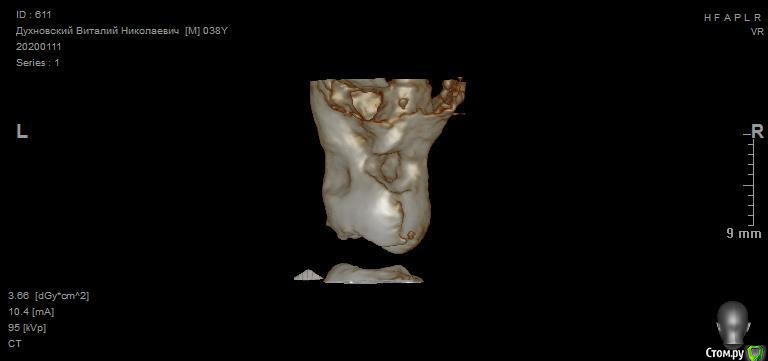

Зуб 27 требует внимания, необходим очный осмотр.

Также стоит обратить внимание на зубы 21 и 24